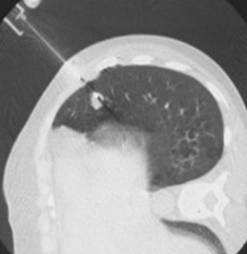

(一)经皮肺穿刺活检术:一叶而知秋

经皮肺穿刺活检为微创诊断肺部疾病的一种方法。许多纤维支气管镜未能取得病理诊断的患者在我科利用经皮肺穿刺活检术得到确诊,弥补了纤支镜的不足,为患者的进一步科学合理治疗提供了支撑。其适应证为:1、肺内结节、纵隔肿块;2、胸壁或胸膜的肿块;3、局灶或多发的肺内突变,感染菌种不明;4、不能手术,但须确定病理类型的肺内恶性病变者。